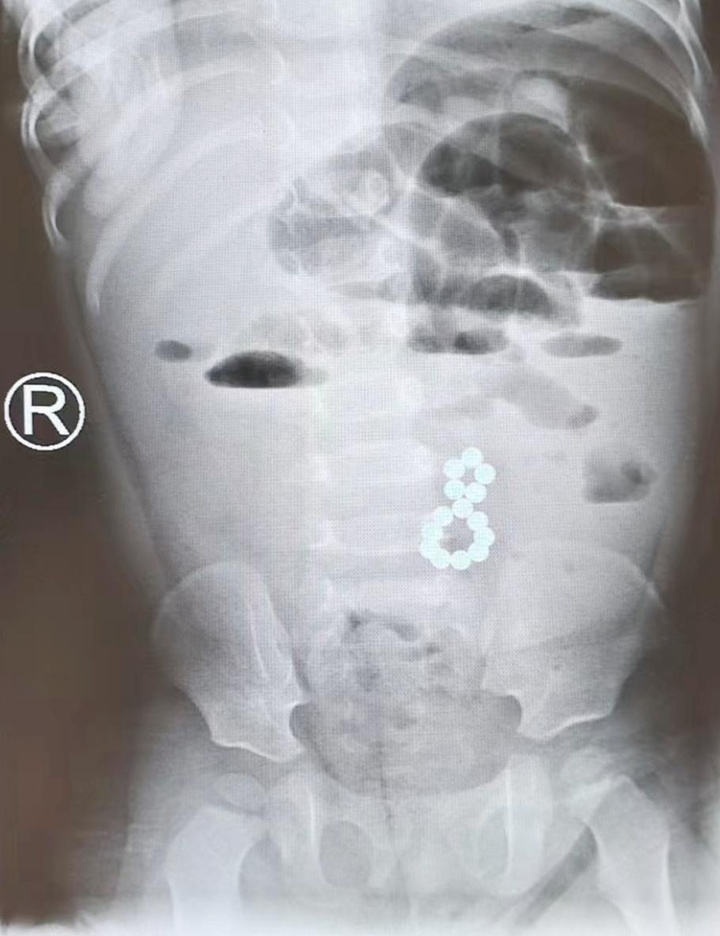

省人医儿科团队接诊后,凭借丰富的临床经验,高度怀疑安安存在消化道异物可能。经紧急腹部X线平片及CT影像学检查,医生确诊安安消化道存在异物。随即小儿外科会诊阅片后考虑异物为磁力小球“巴克球”。更令人揪心的是,影像及临床评估显示,这些磁珠已因相互吸引,导致安安出现肠梗阻,情况已十分危急!

医生在手术中发现,因为磁力珠的强磁吸附,安安的末端回肠出现扭曲,其中2处相互贴合已经形成内瘘,在内瘘两侧肠管内可触及多枚圆形异物。手术团队精细操作,切开内瘘成功取出全部磁性异物,彻底解除了梗阻并修复了瘘口。